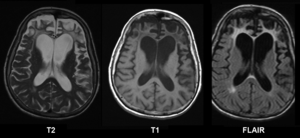

Brain atrophy does not affect all regions with the same intensity as shown by neuroimaging.[2]